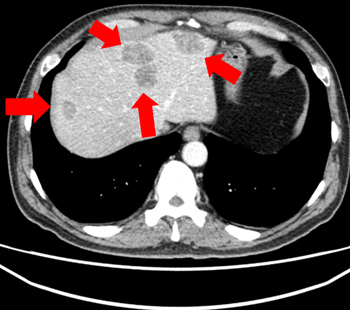

2023.2.2 복부 CT

2025.3.14 복부 CT

※ 동일한 조건에서 촬영된(사진에 대한 별도 조작이 처리되지 않은) 본원에서 진료 및 치료를 받으신 고객(들)의 사진입니다.

사진의 결과는 사례에 기반한 참고 자료로, 개인별 치료 결과는 상이할 수 있습니다.

또한 치료 후에는 홍반, 열감, 피로감, 근육통, 저혈습 등 부작용이 발생할 수 있습니다.